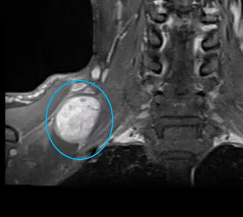

张先生和赵先生住院以后都做了颈部的磁共振检查,检查结果显示张先生的肿块长在了下颌角的边上,肿块还包绕着颈部的大血管。而赵先生的肿块是从臂丛神经上长出来的。

赵先生颈部磁共振